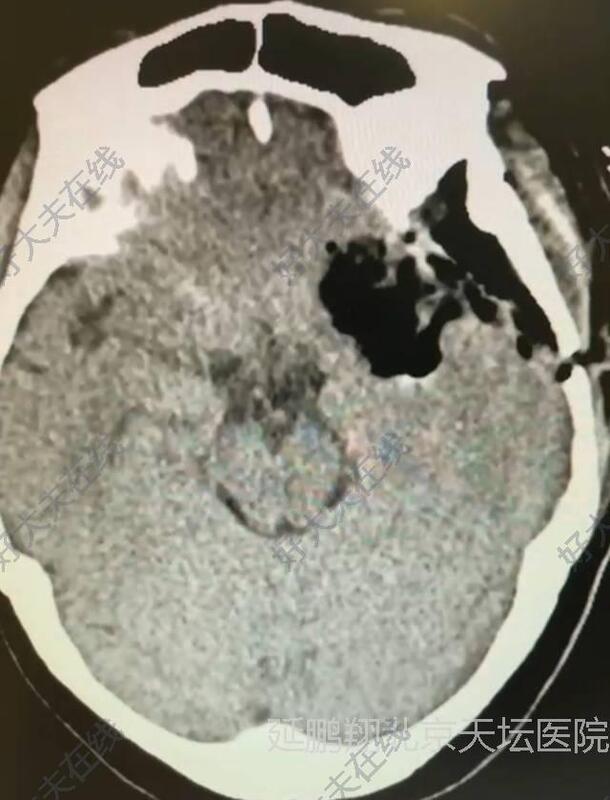

治疗前

患者女性,38岁。间断性头痛3年左眼视力模糊1年。核磁显示左侧前床突脑膜瘤。

病人全麻复苏顺利,清醒后自诉左眼视力明显好转。术后六小时复查CT显示肿瘤消失,瘤腔止血满意彻底。